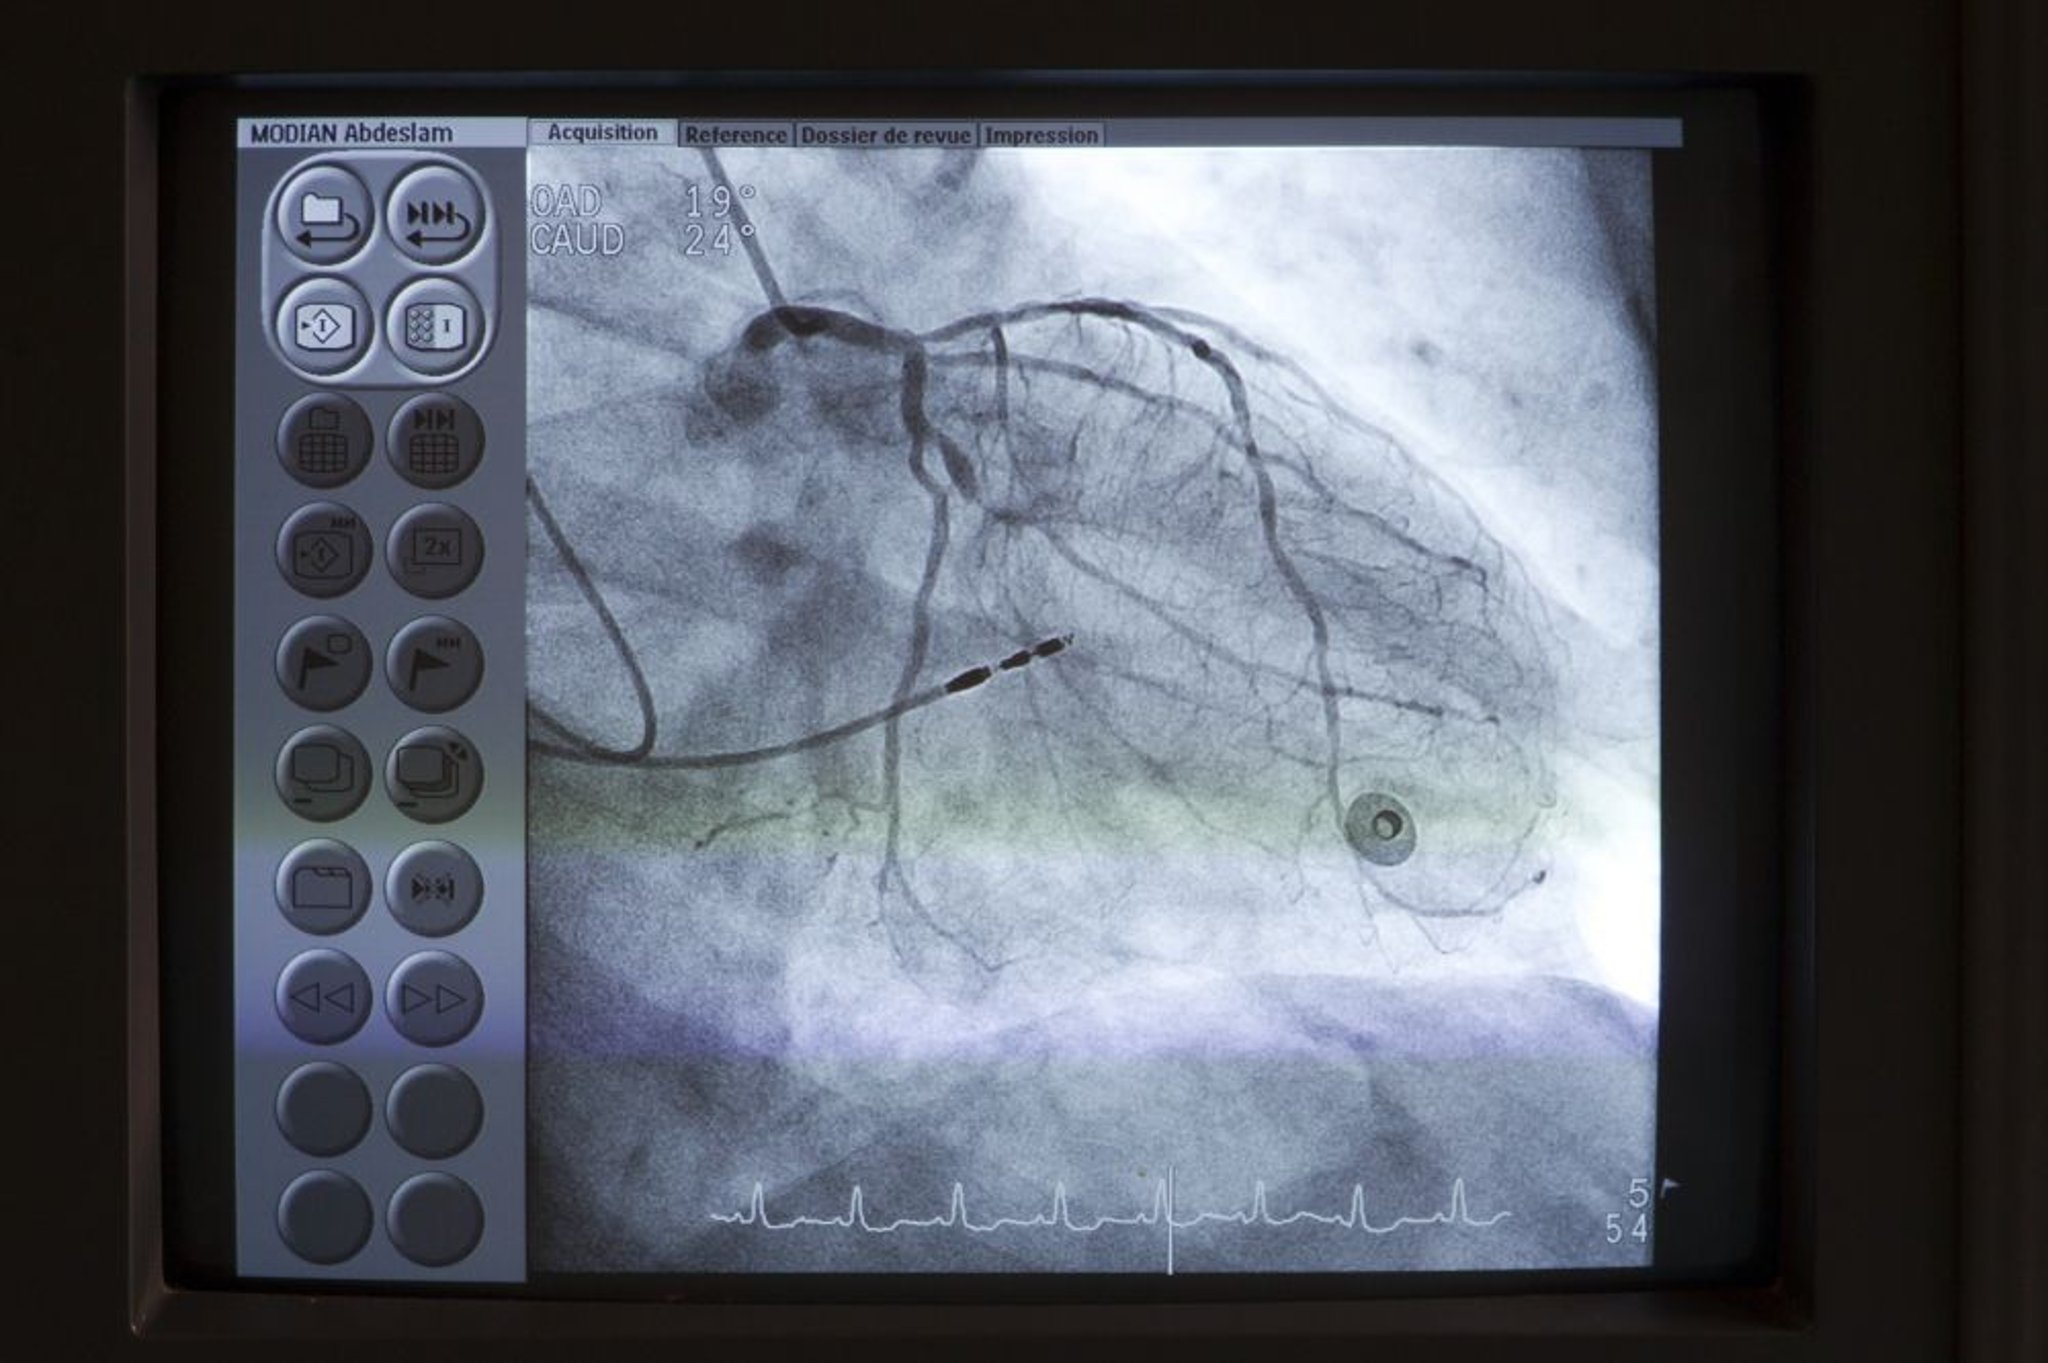

Коронарография

Катетер (вверху слева) устанавливается в главный ствол левой коронарной артерии. Контрастное вещество затем вводится в коронарную артерию с использованием флюороскопии для определения любой патологии, такой как стеноз.

Astier/BSIP/SCIENCE PHOTO LIBRARY